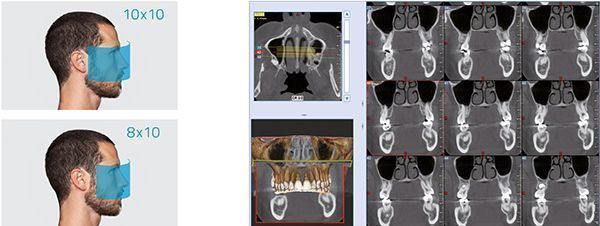

GO 2D/3D это гибкая платформа, готовая к дополнительной интеграции теле радиографического манипулятора в 2D или 3D конфигурации. Способная предоставлять изображения с высоким разрешением, платформа уделяет приоритетное внимание здоровью пациентов благодаря протоколам с низким уровнем экспозиции и эксклюзивной технологии SafeBeamTM, которая позволяет пользователям адаптировать дозу к их фактическим диагностическим потребностям и размеру сканируемой анатомической области. Отличная эргономика и адаптивная система выравнивания обеспечивают правильное позиционирование пациента и идеальную фокусировку для четких и детальных изображений. Виртуальная панель управления проведет оператора через каждый этап обследования. NNT-это технологически продвинутая программная платформа для управления, обработки, консультирования и обмена диагностическими изображениями.

Детализированные объемы для всех клинических задач с заботой о здоровье пациентов

Учитывая природу цефалометрического обследования, часто применяемого в детской стоматологии, NewTom разработал протокол, минимизирующий дозу рентгеновского излучения, которому подвергается пациент. Со временем сканирования всего в 3,7 с, пациент получает пользу от минимального облучения и крайне малого времени пребывания внутри аппарата. Помимо режима сканирования удлиненная защита ушей защищает щитовидную железу ребенка от необязательного облучения при осмотре.

- ECO SCAN И АДАПТИВНОЕ ПОЛЕ ОБЗОРА